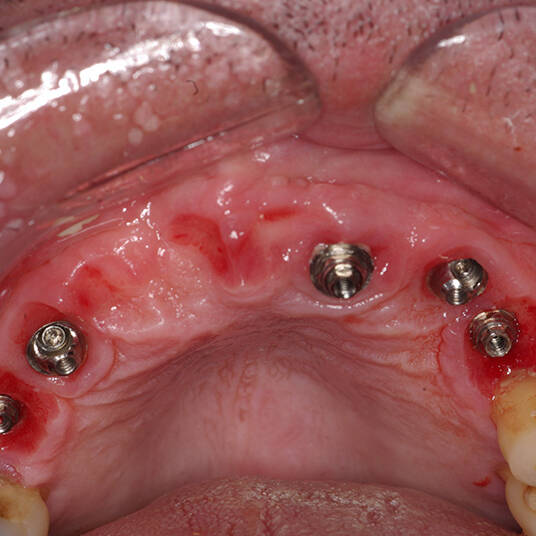

A reabilitação oral é um conjunto de tratamentos odontológicos que combina próteses dentárias, técnicas estéticas e terapias restauradoras. O principal objetivo desse procedimento é devolver ao paciente a capacidade de mastigar, falar e sorrir com confiança. Além disso, é fundamental para a saúde bucal, já que remove infecções e corrige problemas funcionais.

A reabilitação oral é um dos procedimentos mais completos da odontologia, envolvendo várias especialidades como prótese dentária, implantodontia e periodontia. Esta integração permite restaurar a saúde bucal de forma global, garantindo que o paciente recupere a função mastigatória, a harmonia estética e a saúde oral.